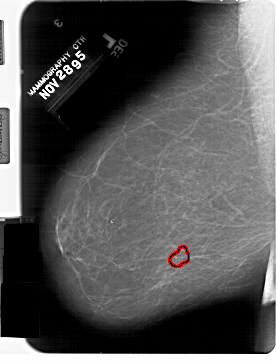

FILE: A_1332_1.LEFT_MLO.OVERLAY

TOTAL_ABNORMALITIES 1

ABNORMALITY 1

LESION_TYPE CALCIFICATION TYPE PLEOMORPHIC DISTRIBUTION CLUSTERED

ASSESSMENT 4

SUBTLETY 2

PATHOLOGY BENIGN

TOTAL_OUTLINES 1

BOUNDARY